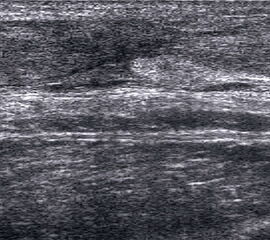

Tendopathien der Flexorensehnen

Dorsaler TS hinter dem Innenknöchel.

Abbildung 46

Lagerung: Rückenlage, Außendrehung des Beines.

Schnittführung: TS und LS hinter dem Innenknöchel beginnen und bis zum Os cuneiforme mediale fortführen.

Referenzstrukturen: Innenknöchel, Talus, Os naviculare, Os cuneiforme mediale, Sehnen der Mm tibialis posterior, flexor hallucis longus, flexor digitorum.

Befunde: Häufig betreffen die Pathologen die Tibialis-posterior-Sehne, die als erste Sehne hinter dem Innenknöchel zur Darstellung kommt. Halo-Phänomen und echoarme Verdickung bei akuter Tendinopathie, zunehmend inhomogen und echogen mit Kaliberschwankungen bis hin zu Teilrupturen bei Chronifizierung 5. Für die Erkennung von Teilrupturen sind TS in verschiedener Höhe besonders wichtig. Bei komplettem Riss mit Retraktion im LS Bild wie Spargelspitze mit umgebender Flüssigkeit oder Hämatom. Ein Os tibiale externum erscheint als echoreiche Struktur im Verlauf der Tibialis posterior Sehne mit dorsaler Schallauslöschung. Ein Os naviculare cornutum imponiert als starke Prominenz im Ansatzbereich der Tibialis posterior Sehne.